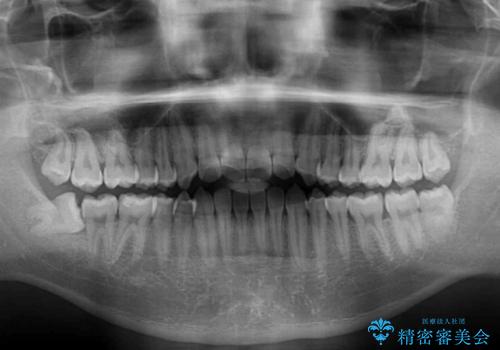

- 上下前歯のデコボコを気にして来院された患者様です。

叢生は軽微であり、費用を抑えて期間もあまりかけずに治療をしたいとのことで、インビザライン・ライトを用いて矯正治療を行うこととしました。